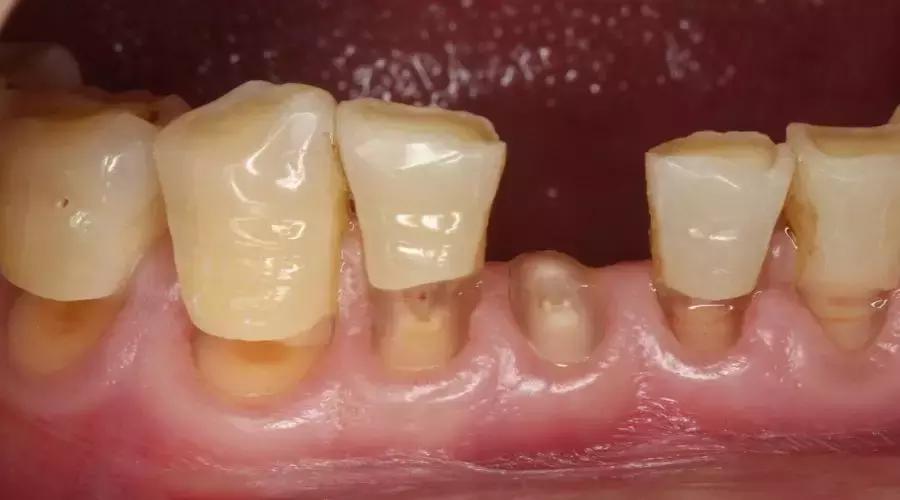

大白突然想到自己相机里还有一张照片:就是这种问题最严重状况——可能会导致牙齿「拦腰折断」!

图片由作者提供

折断当然是少数,大多还是处在前面那种「刚好把手指甲卡进去」的程度,好奇的大家可以自己感受一下试试?

➌「打桩」修复或拔牙

更严重的情况,缺损「横腰」截断了牙齿,牙齿折断(或者即将折断),那么很抱歉,牙医很可能要在这个牙根上面「打个桩」,然后再用假牙修复起来。而最坏的情况是:很可能牙医也留不住这个牙齿,不得不拔掉。